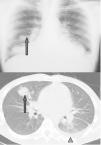

La neumonía lipoidea exógena es una entidad poco frecuente que clásicamente se ha considerado como un proceso crónico secundario a la aspiración o inhalación continuada de sustancias grasas. En ocasiones puede presentarse una forma aguda, coincidiendo con una única y masiva aspiración de material lipídico, siendo un accidente característico de los artistas callejeros o circenses que exhalan fuego («comedores de fuego») y que puede generar una insuficiencia respiratoria aguda. En este trabajo se presentan las manifestaciones clínicas, las pruebas complementarias y la evolución de dos casos de neumonía lipoidea exógena aguda tras inhalación de derivados del petróleo en «comedores de fuego». Mientras para el diagnóstico de las formas crónicas pueden ser necesarias exploraciones complementarias invasivas, el antecedente de inhalación reciente de sustancias grasas suele facilitar el diagnóstico en las agudas. La evolución de las formas agudas suele ser favorable, aunque se han descrito neumonías que evolucionan hacia la cavitación, el distrés respiratorio y la muerte. El tratamiento se basa en medidas sintomáticas de soporte.

Exogenous lipoid pneumonia is a rare disease that has traditionally been considered a chronic condition secondary to continued aspiration or inhalation of fatty substances. An acute form may sometimes appear after a single and massive aspiration of lipid material, being a characteristic accident of street artists or «fire-eaters» that may generate acute respiratory failure. In this paper, we present clinical and radiological signs and outcome of two cases of lipoid pneumonia in «fire-eaters». A few hours after exposure patients may develop fever, cough, chest pain, hemoptysis, pulmonary infiltrates or hypoxemia. While diagnosis of chronic forms may require invasive procedures, recent exposure to fatty substances is a clue for clinical diagnosis in acute forms. Acute forms usually have a good outcome but cases evolving to cavitary pneumonia have been described. Some patients can present with acute respiratory distress syndrome and death. Treatment is based on general supportive measures.